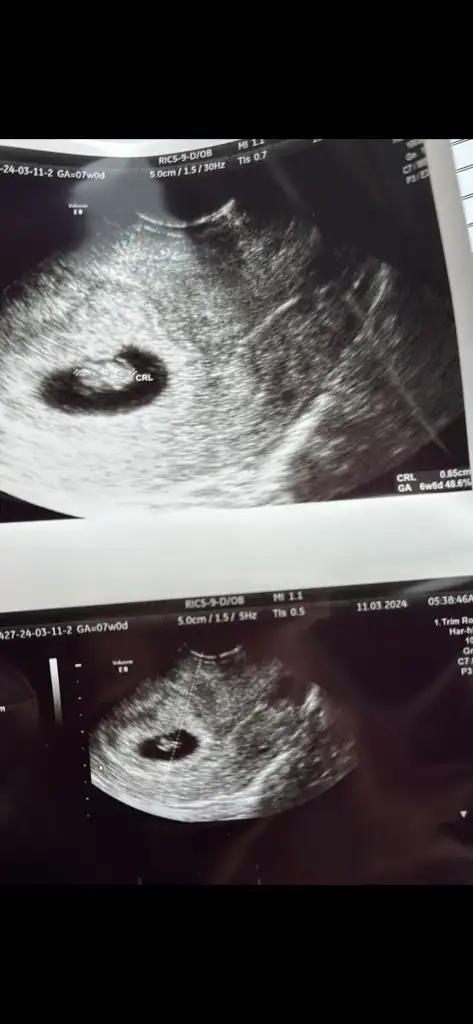

Ultrason görüntüsünü de ekliyorum anlayan olursa belki

Normalde 7+5 bugün ama ultrasona göre bebek 6+5 dedi